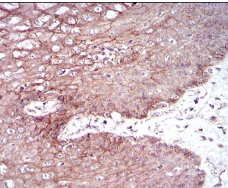

IHC    1/200 - 1/1000